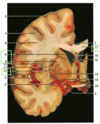

Label 5, 6 & 7

1 - superior temporal gyrus;

2 - inferior frontal gyrus; 3 - insular cortex;

4 - temporal stem;

5 - internal capsule;

6 - thalamus;

7 - lentiform nucleus (the internal and external globus pallidus and the putamen)

8 - frontal horn;

9 - superior circular sulcus;

10 - inferior circular sulcus.